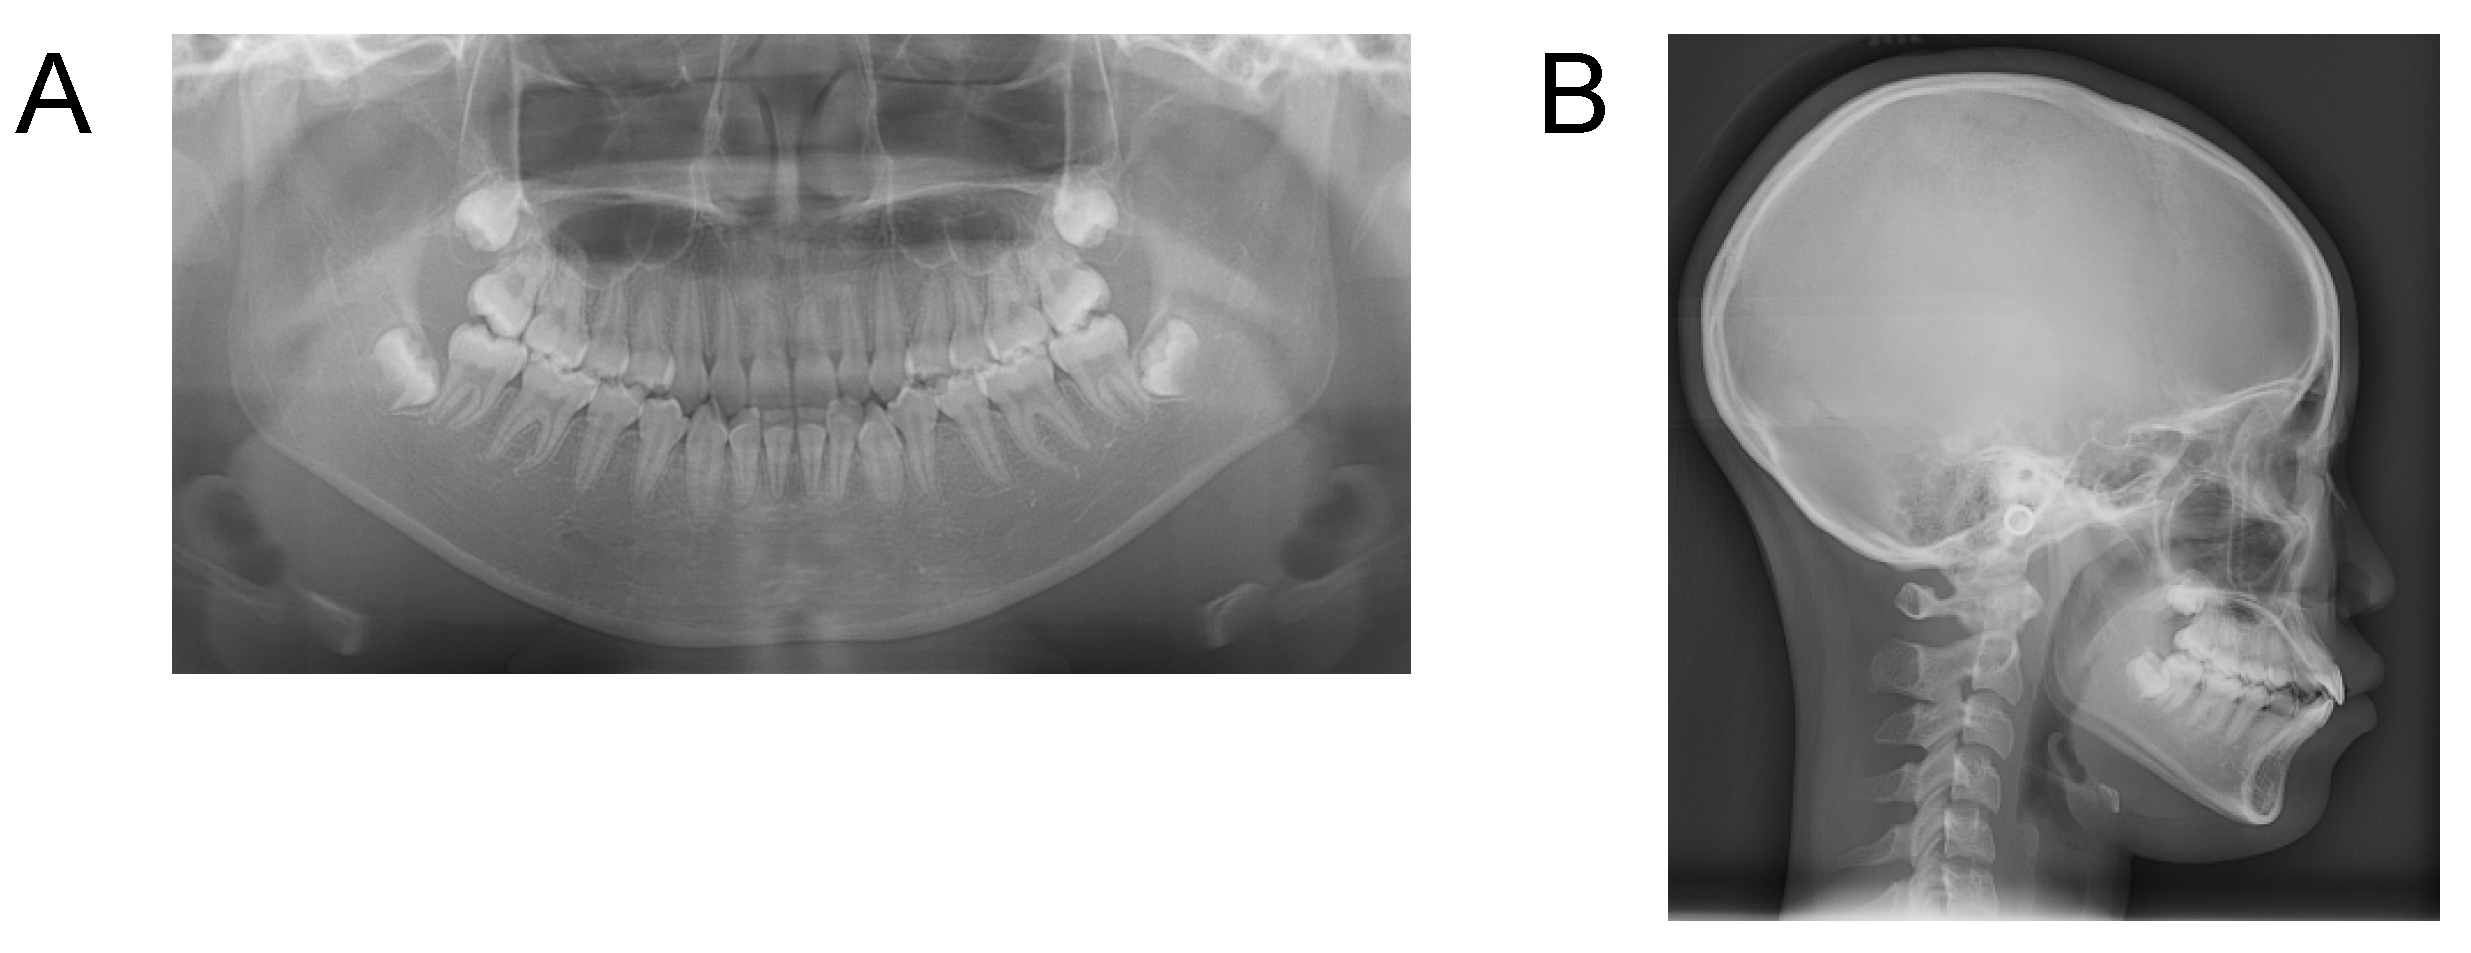

Case 3. Findings from initial examination